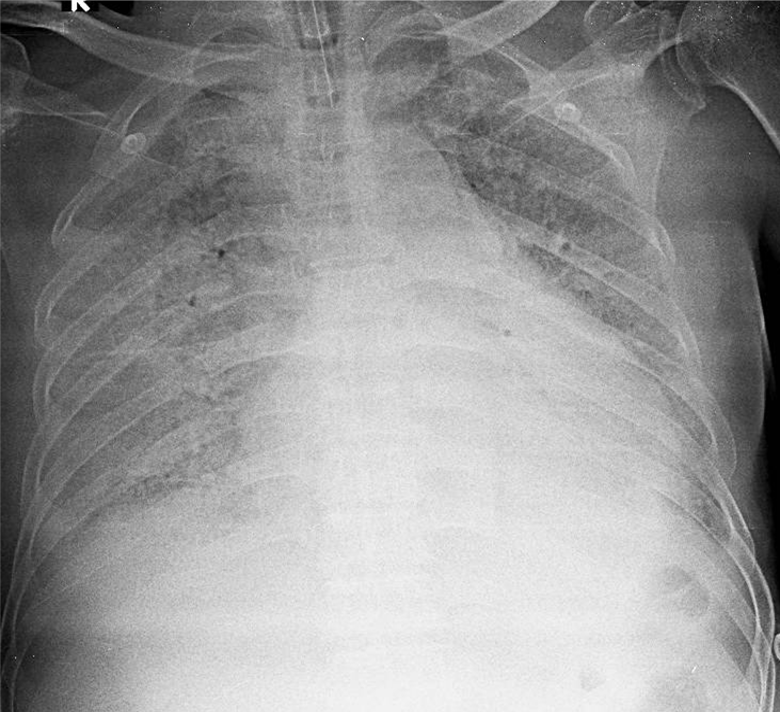

Hãy phân tích tình huống nữ 70 tuổi

1-Đang đặt nội khí quản 2-Tổn thương mô kẻ rải rác hai phổi => Viêm phổi, lao kê, ... 3-Tim to